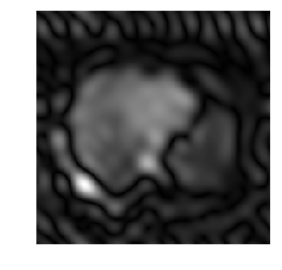

Medical image segmentation methods normally perform poorly when there is a domain shift between training and testing data. Unsupervised Domain Adaptation (UDA) addresses the domain shift problem by training the model using both labeled data from the source domain and unlabeled data from the target domain. Source-Free UDA (SFUDA) was recently proposed for UDA without requiring the source data during the adaptation, due to data privacy or data transmission issues, which normally adapts the pre-trained deep model in the testing stage. However, in real clinical scenarios of medical image segmentation, the trained model is normally frozen in the testing stage. In this paper, we propose Fourier Visual Prompting (FVP) for SFUDA of medical image segmentation. Inspired by prompting learning in natural language processing, FVP steers the frozen pre-trained model to perform well in the target domain by adding a visual prompt to the input target data. In FVP, the visual prompt is parameterized using only a small amount of low-frequency learnable parameters in the input frequency space, and is learned by minimizing the segmentation loss between the predicted segmentation of the prompted target image and reliable pseudo segmentation label of the target image under the frozen model. To our knowledge, FVP is the first work to apply visual prompts to SFUDA for medical image segmentation. The proposed FVP is validated using three public datasets, and experiments demonstrate that FVP yields better segmentation results, compared with various existing methods.